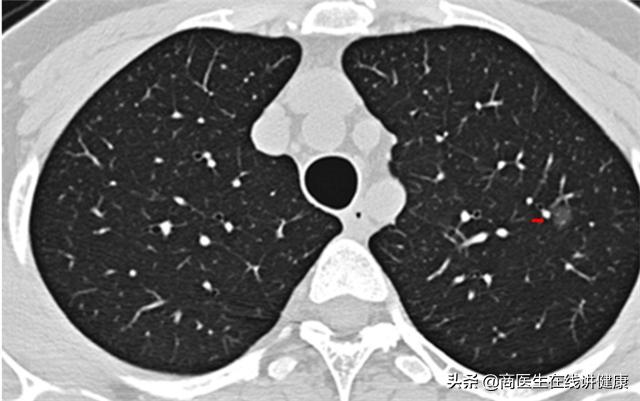

经过对患者叶女士询问后,我们首先推荐患者去做胸部CT。拿到CT结果后,发现患者果然在 双肺多处均有结节状影像,存在多发性结节的情况。从CT上看,结节的大小和实性均不一。但从大小上看,都属于微小结节,且性质上也均属于毛玻璃状。

连续入院治疗十天后,患者叶女士咳嗽及咳痰等症状已明显缓解 ,随后再次做了肺部CT复查,CT检查结果显示,多个肺部结节已经通过治疗后消失,仅有右肺下叶处一个结节仍在影像结果中有显示,但对比入院的CT结果来看,此结节的影像也有所变淡,但大小并无明显变化。